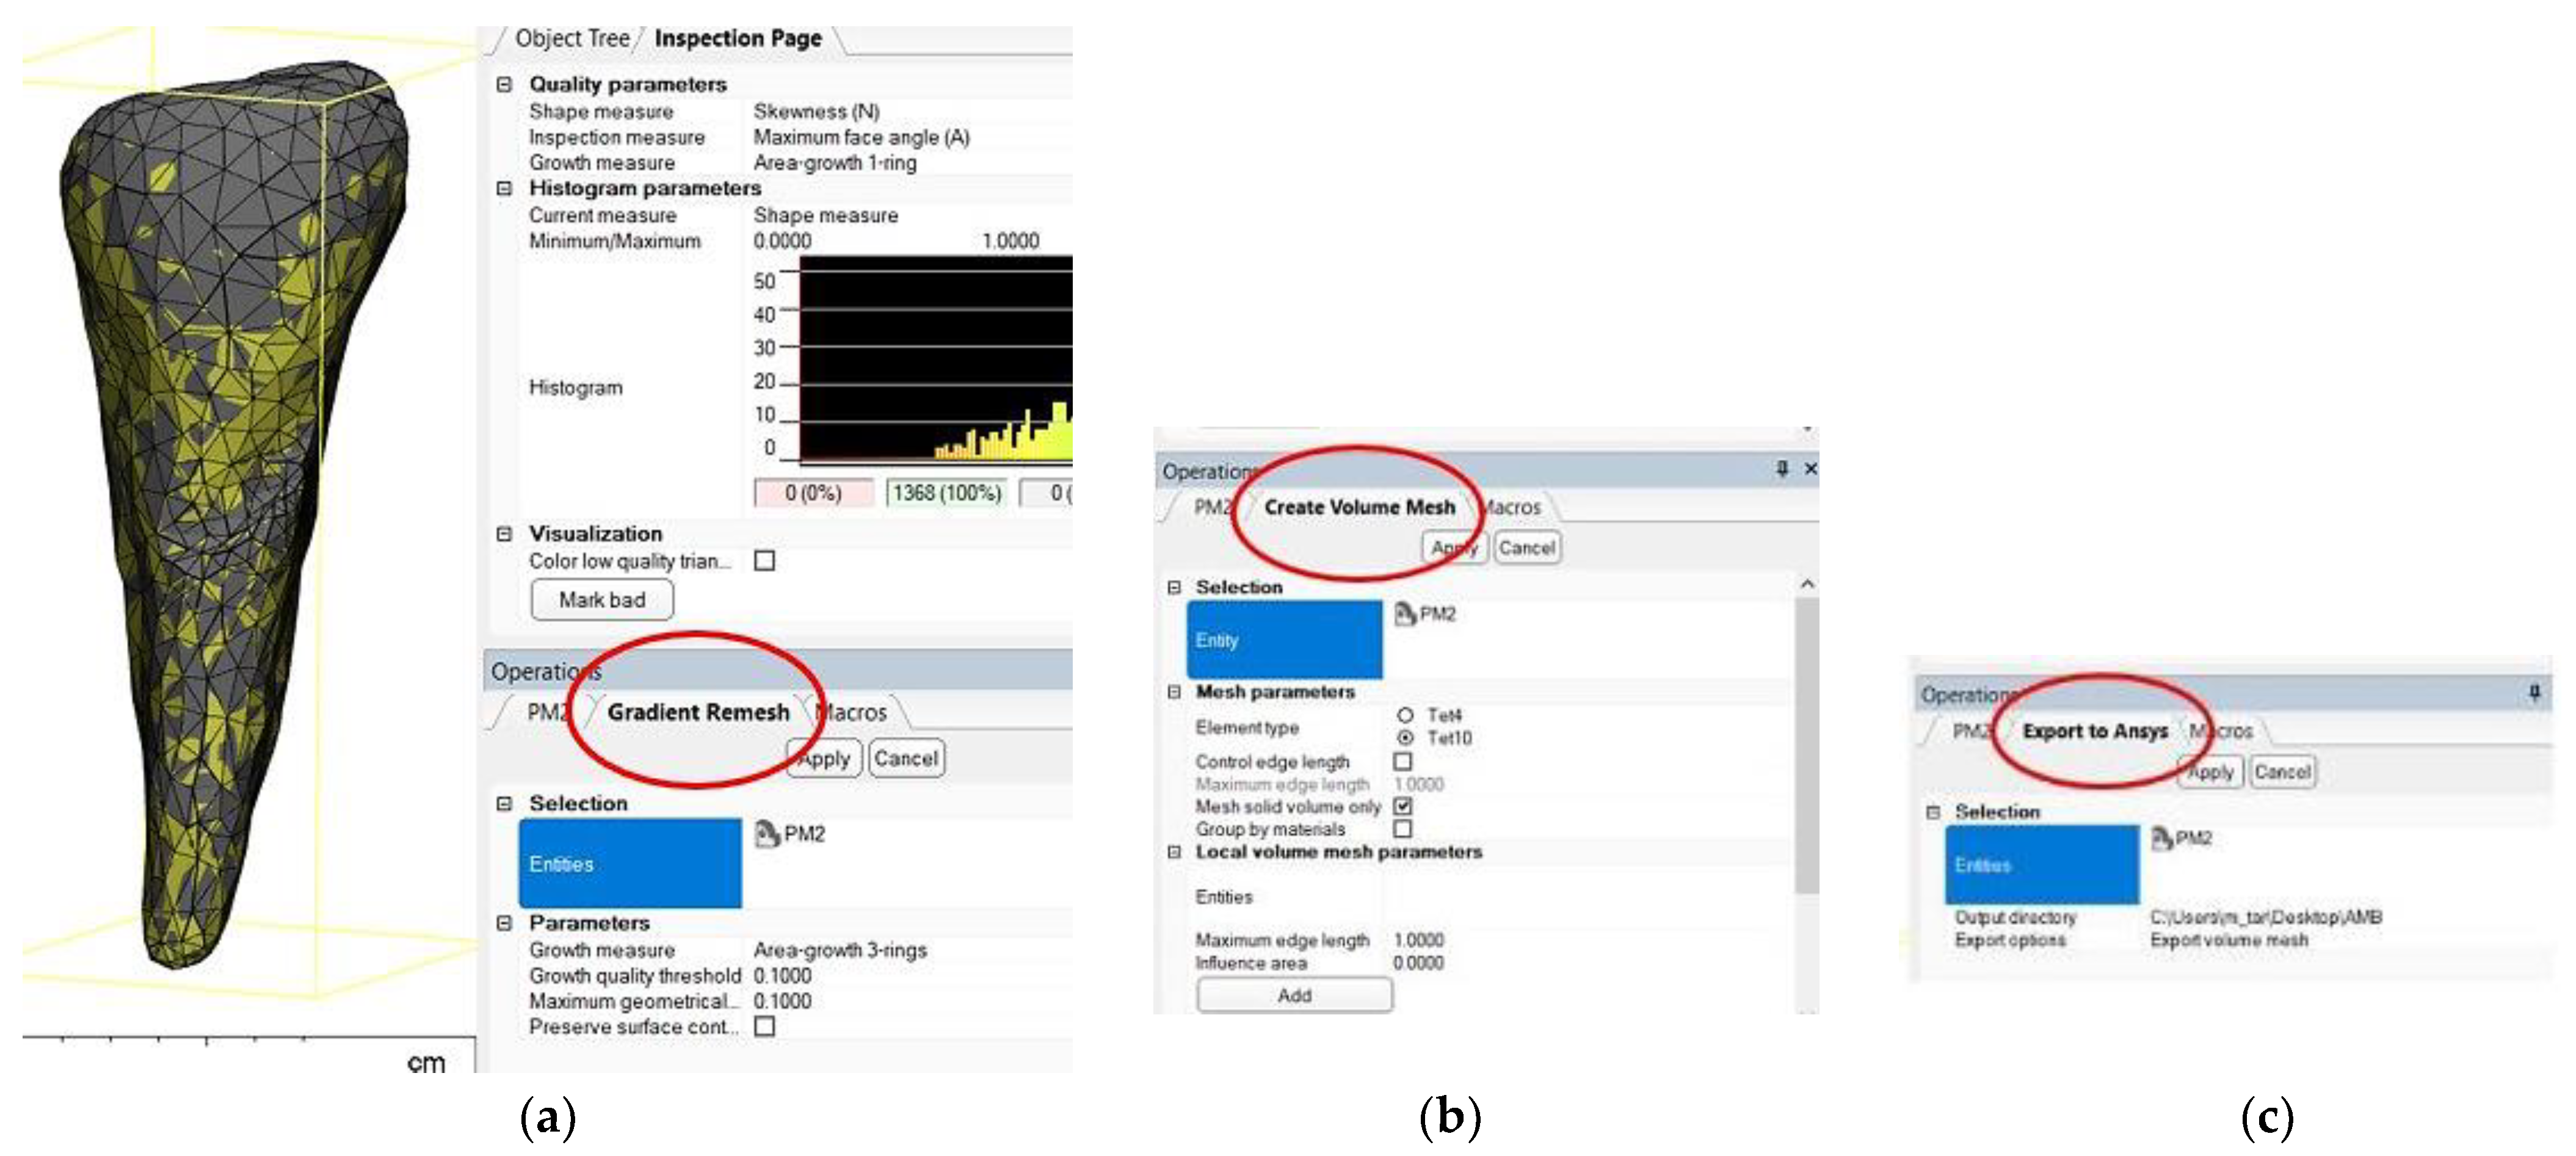

3. Finite Element Analysis (FEA) of Mandibular Right Premolars